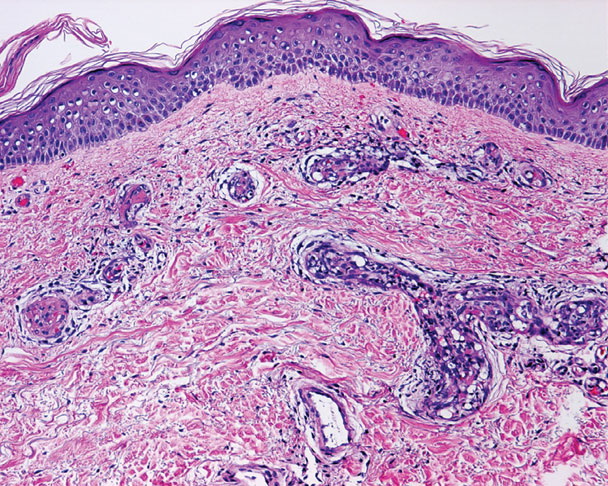

Angiomatosis. Vascular proliferation =التكاثر وعائي __التوعي